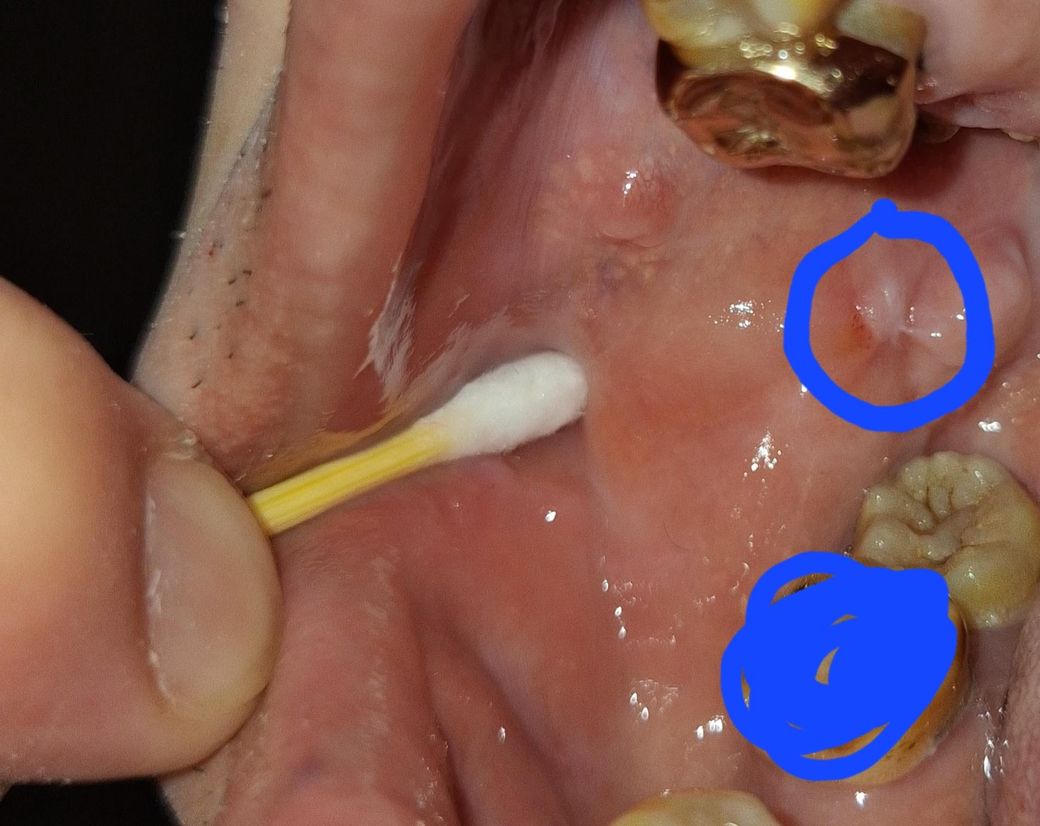

우측 볼점막에 우연히 양치를 하다가 발견했습니다 아프지는 않습니다

혹시 구강암은 아닌지 염려가 됩니다

지금 상태가 구강암 증상인가요?

사진이 명확하지 않아서 정확한 말씀 드리기 어려운점 양해부탁드립니다. 사진만 봐서는 백반증이나 과각화증 등 의심가능해보이며 해당부위에 대한 정확한 임상검사 및 필요 시 조직검사 등을 요할 수 있습니다. 걱정되신다면 근처 구강악안면외과 또는 구강 내과 등 내원하시기를 바랍니다.

꼭 악성병소라고 단정지을만한 상황은 아니지만 구강내과를 한번 가보는 것을 추천합니다 일단 사진상으론 볼을 씹어서 생긴 궤양이거나 아니면 감염병소로 보입니다